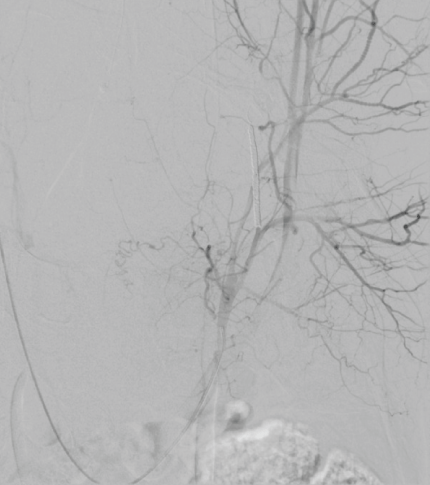

Seven hours after undergoing an uneventful TVT insertion under local anesthesia a 55-year-old non-obese para 2 woman was brought to the emergency department complaining of lower abdominal pain and vertigo. On physical examination, she was alert and aware, but pale, peripherally cold and hypotensive (blood pressure was 80/30 and pulse = 55/minute). Apart from medical treatment for hypertension, she was healthy. Prior surgical history included an appendectomy only. On suspicion of intraperitoneal bleeding, laparoscopic evaluation was performed showing a large hematoma retropubically and on the posterior abdominal wall and after conferral with a vascular surgeon, the decision was made to perform arterial embolization. The subsequent angiography localized significant bleeding from the right obturator artery; an anterior branch of the internal iliac vessel (Figure 1) and a retropubic hematoma 17.5 cm × 10.0 cm in size (Figure 2). The patient was treated by selective embolization with coils of the right obturator artery (Figure 3) and her vital signs remained stable after the procedure. Five days postoperatively, the patients presented with fever of 38.9 ºC and diffuse lower abdominal pain. She received intravenous broad-spectrum antibiotics, the pain abated and an enhanced Computed Tomography (CT) scan revealed a reduced hematoma sized 11 cm × 6 cm. To prevent formation of an abscess and due to ongoing fever (temperature up to 38.9 ºC) laparoscopic evacuation of the hematoma was performed with a total blood loss of 1000 ml on postoperative day 10. Because the upper part of the tape had loosened from the tissue and was visible intraperitoneally, this part had to be removed.

Figure 3: Pelvic arteriography after embolization of the right obturator artery. View Figure 3